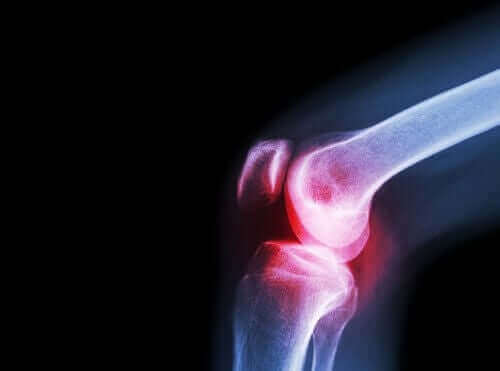

Slidgigt

Læger anbefaler aceclofenac til denne tilstand også. Slidgigt er en anden reumatisk sygdom, som skader brusk i led.

Leddene indeholder en væske, der er kendt som synovial væske, som det synoviale membran producerer. Spidserne af knoglerne, som mødes for at danne leddene, er dækket af artikulært brusk.

Når denne brusk oplever skade, forårsager det smerte, stivhed og funktionelt handicap. Det er derfor vigtigt at differentiere denne sygdom fra leddegigt. Den sidstnævnte udvikler sig på grund af inflammation i led, ikke slid af brusk.

Eftersom de begge forårsager smerte, er aceclofenac dog effektivt til behandlinger af symptomerne, som de begge forårsager.